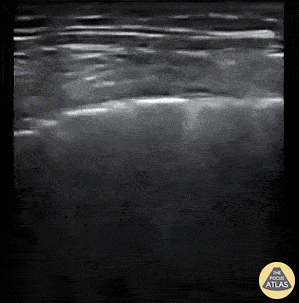

Pleural Findings in COVID-19

B-Lines w/ irregular pleura and consolidations